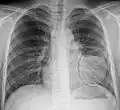

Normal AP CXR

AP CXR showing pneumonia of the lingula of the left lung -

Left upper lobe pneumonia with a small pleural effusion.